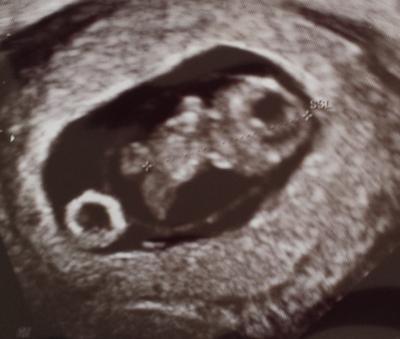

Hallo ihr Lieben, Ich komme gerade vom FA zurück und habe ganz vergessen ihn zu fragen um was es sich bei der "Schraubenmutter/Fussball" handelt... kann mir jemand von euch sagen was das ist? Ich denke ihr wisst was ich auf dem Bild meine Liebe Grüße

Ich tippe auf DotterSack

Das ist der Dottersack.